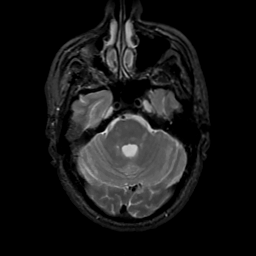

MR Study #7, March 24, 1991 -- Slice #13